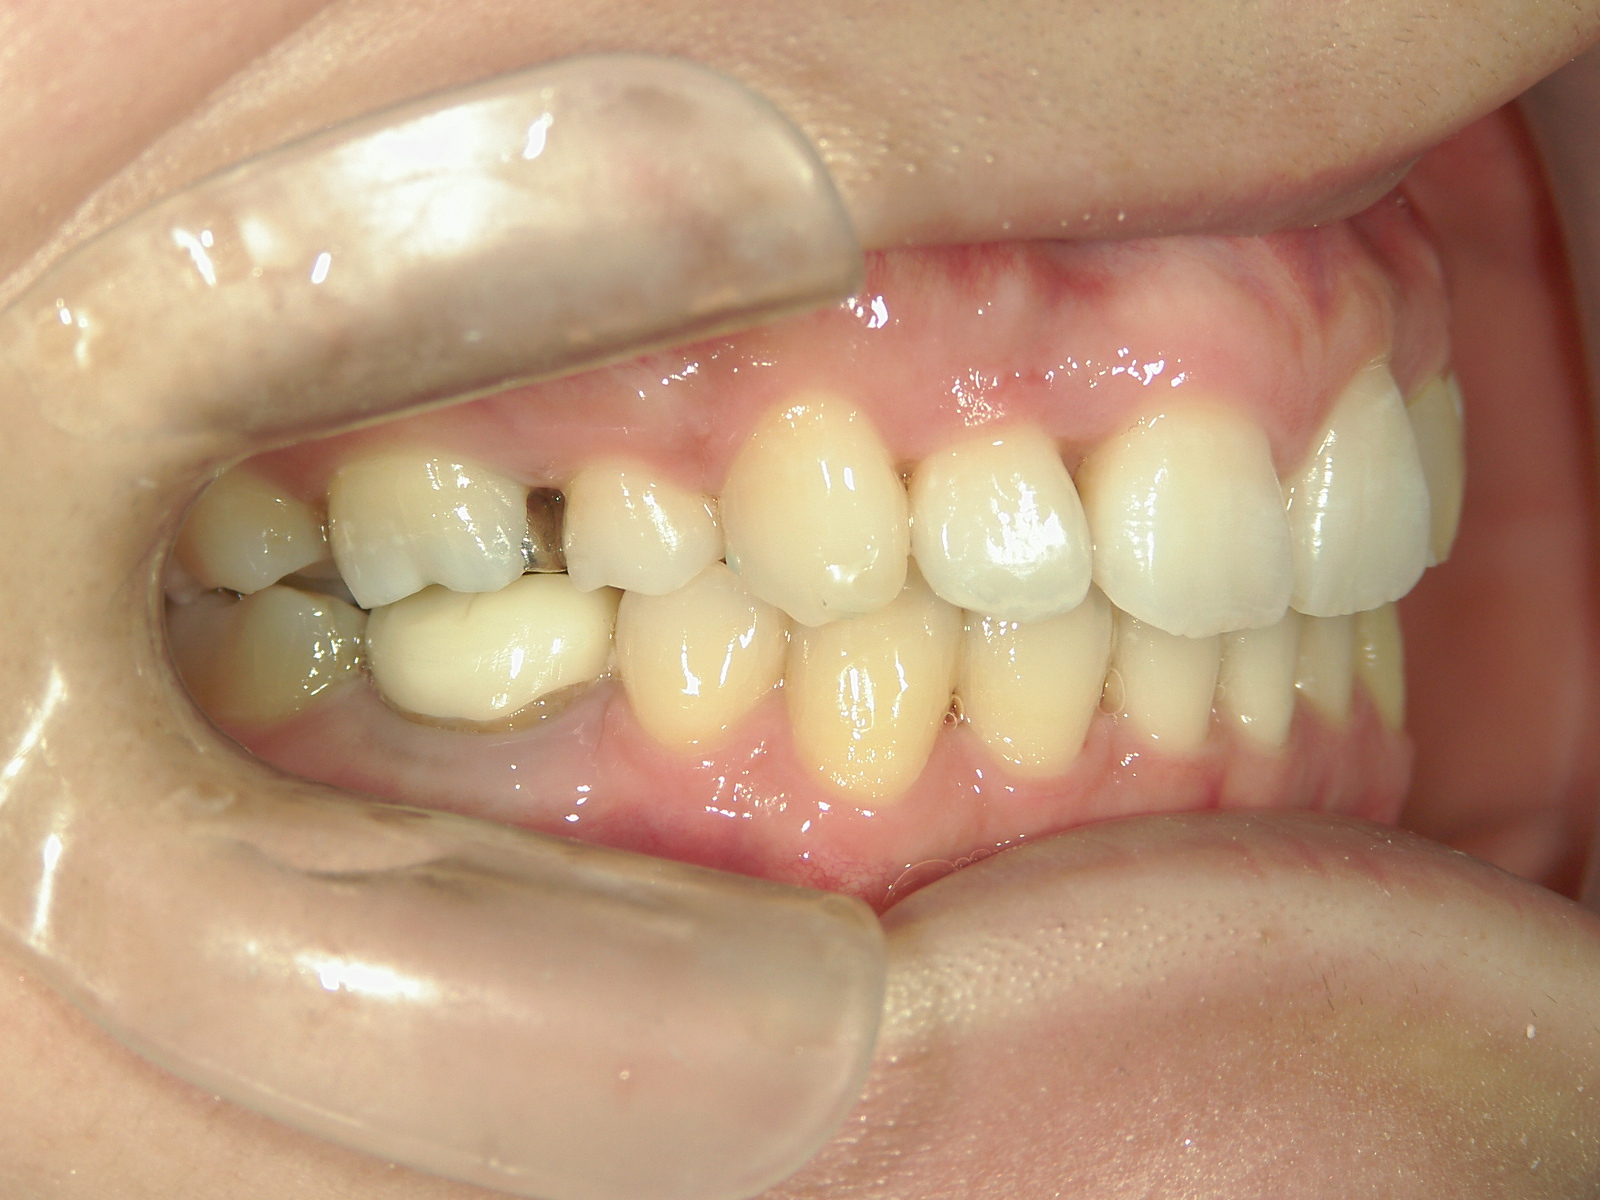

舌側ワイヤー矯正 症例(25)

主訴: 歯並びが気になる

カテゴリー : ガタガタ(叢生)